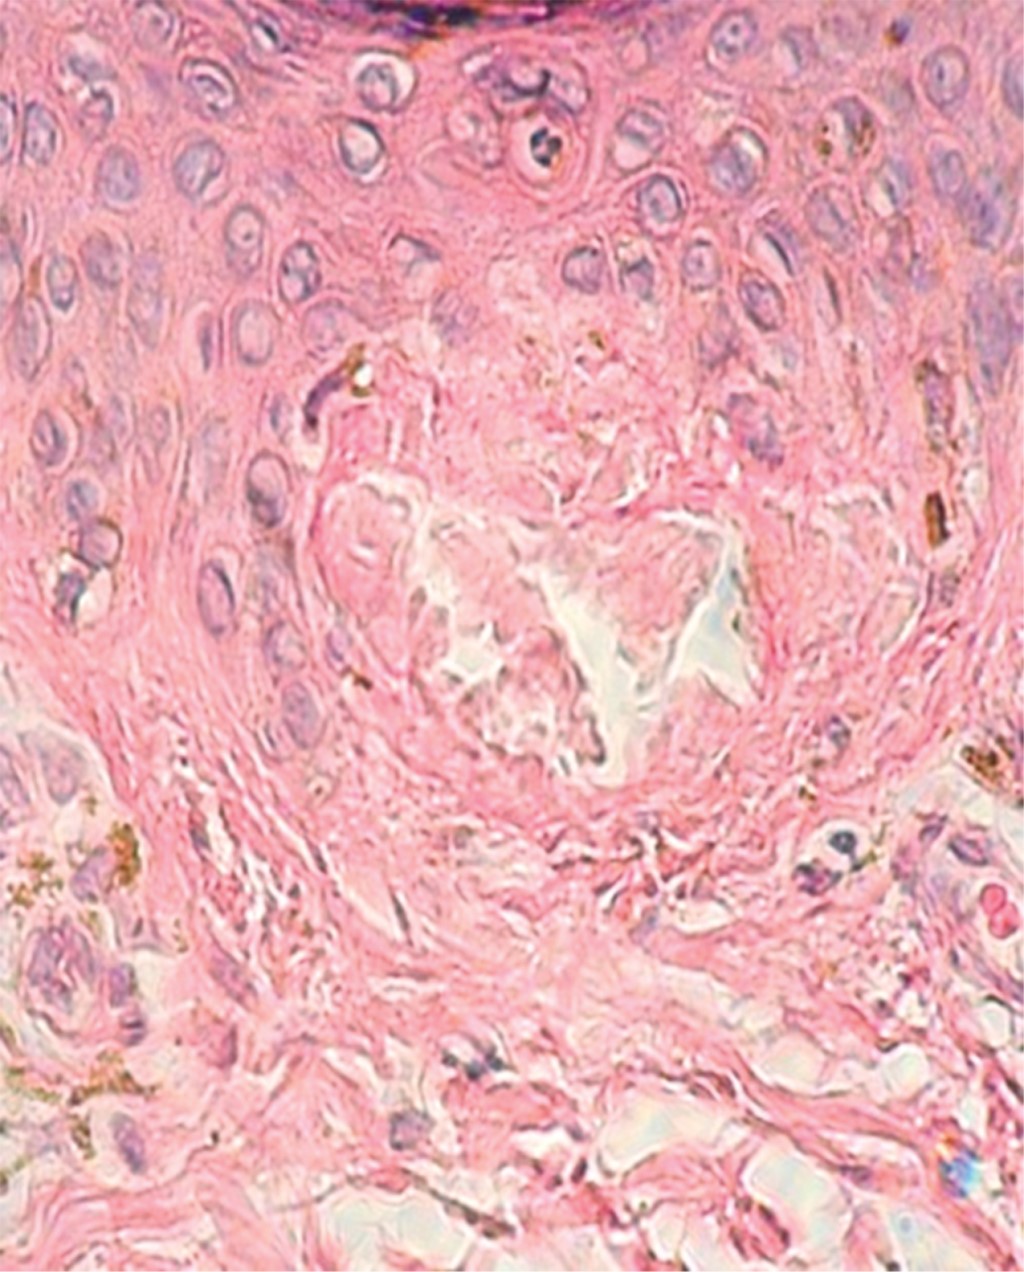

Se trata de una mujer de 37 años de edad, empleada, originaria y residente de la Ciudad de México, quien acude a valoración en la consulta del Centro Dermatológico "Dr. Ladislao de la Pascua" por presentar lesiones que aparecieron 11 años antes, intensamente pruriginosas. Sin antecedentes de importancia para su padecimiento. Negó tratamientos previos. A la exploración física se observa dermatosis diseminada a extremidades inferiores, de las que afecta cara anterior de piernas casi en su totalidad, dejando sólo algunas áreas de piel sana, de aspecto monomorfo, monolesional, constituida por incontables pápulas milimétricas, color marrón oscuro, agrupadas en un patrón de aspecto reticular. De evolución crónica y muy pruriginosa (Figura 1). A la dermatoscopía se observa depósito de pigmento con distribución aleatoria (Figura 2). En el resto de piel y a nexo s no se encontraron datos patológicos. Se realiza biopsia incisional, cuyos cambios histológicos se observan en las Figuras 3 y 4.

La histopatología de ambos tipos muestra depósitos de amiloide agrupados en pequeños glóbulos que ocupan la dermis, así como incontinencia del pigmento.2 En la mayoría de los casos con el empleo de las tinciones de rutina es suficiente para realizar el diagnóstico; ahora bien, existen otras tinciones, como rojo congo, las cuales son más específicas y definitivas. Con esta última técnica el material amiloide se tiñe de color verde birrefringente utilizando el microscopio de luz polarizada.1